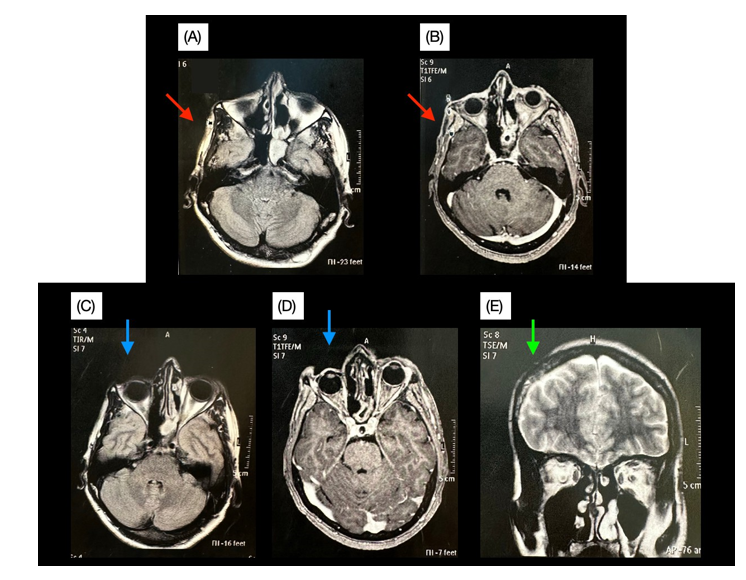

Figure 3 (A) and (C) T2-Flair MRI showing myocutaneous atrophy, involving masseter and temporal muscles (red arrow) and enophthalmos (blue arrow). (B) and (D) T1 MRI with contrast showing facial asymmetry (red arrow) and enophthalmos (blue arrow). (E) Represents coronal-T2 plane, showing cutaneous/subcutaneous atrophy (green arrow).

Male patient, 40 years old, diagnosed at 31 years of age with SPR, presenting atrophy in the entire right hemiface, extending to the right parietal region and lagophthalmos. He used penicillamine 1 g/day for 6 months and methotrexate 20 mg/week for 5 years, in addition to aesthetic procedures, a few years after diagnosis. Undergoing ophthalmological follow-up using artificial tears. He began follow-up with a complaint of recurrent and disabling holocranial headache.4 Brain MRI showed enophthalmos on the right, atrophy of the subcutaneous tissue and of the masseteric and temporal muscles on the right, in addition to foci of signal alteration in the periventricular white matter of the right cerebral hemisphere. The headache was chronic, disabling and refractory to the continuous use, for more than 1 year, of amitriptyline 75 mg/day and valproic acid 2 g/day, either alone or in combination. The patient had a Headache-Related Disability Index (HDI-Brazil) score of 88 and a Headache Impact Test (HIT-6) score of 72, generating a significant negative impact on quality of life. Cannabis sativa promediol extract 200 mg/mL (CBD* + THC** combination) was prescribed at a dosage of 35 mg of CBD per day (7 drops every 8 hours), in combination with valproic acid 2 g/day and amitriptyline.5 After 3 months of continuous use of Cannabis sativa promediol extract associated with the anticonvulsant, both questionnaires HDI-Brazil and HIT-6 decreased to 56 points, with a significant improvement in the patient's quality of life. After 7 months of using the Cannabis extract, there was a decrease in the dose of valproic acid to 1.5 g/day, without compromising the improvement acquired (Figure 1-3).6,7